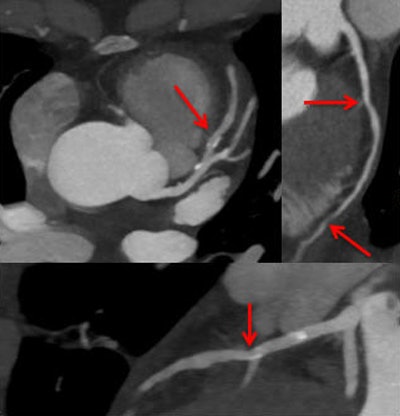

When people refer to MPI, they're actually talking about a variety of techniques -- but the principal dividing line in CT is between so-called static perfusion CT angiography and dynamic perfusion CT. Both can be performed with single-energy or dual-energy CT. Neither actually measures perfusion, but rather surrogates for it that examine iodine distribution at the point where the information is acquired, explained Henzler, who is chief of cardiothoracic imaging at the University Hospital Mannheim.

Static perfusion CT is hampered somewhat by the density of the myocardium itself, meaning that it's impossible to really discern how much density was contributed by the iodine. This limitation confers a small advantage on dual-energy CT because it enables the reader to selectively visualize the amount of contrast in the volume, he said.

Iodine distribution in the myocardium roughly corresponds to the arterial input function, and as a result, coronary CT angiography (CCTA) exams create a moment of peak enhancement in the myocardium, according to Henzler. This means a static or snapshot perfusion imaging technique may be sufficient, because it is at the time of peak enhancement that the small differences between normal and ischemic myocardium are maximized.